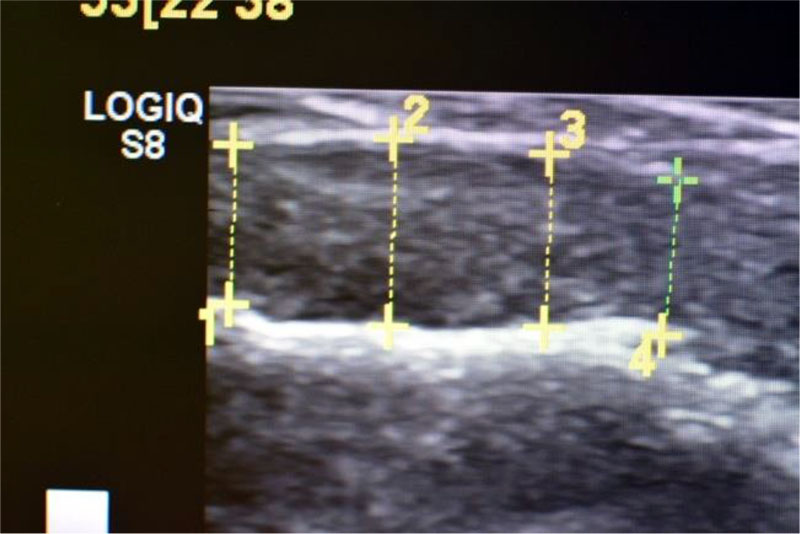

Figure 1. Installation of an intraoperative linear transducer L 8-18i - RS (8-18 MHz) wrapped in one layer of cling film in the hard palate (RF Patent No. 2722055 dated May 26, 2020).

Figure 2. Registration of the obtained indicators of the thickness of the soft tissues of the oral cavity on the monitor screen during the ultrasound examination (RF Patent No. 2722055 dated May 26, 2020).

The biotype of the gingiva was determined using a non-invasive ultrasound examination using a specially developed method (RF Patent No. 2722055 dated May 26, 2020) (Fig. 1a, 1b). If the thickness of the gingiva is less than 1 mm, the biotype was considered thin; from 1.0 to 1.5 mm - average, when registering indicators over 1.5 mm, the biotype was considered thick [2].